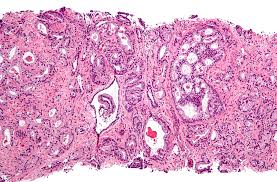

The prostate is a gland in the male reproductive system that surrounds the urethra just below the bladder. Because of this, many men with prostate cancer will. Some prostate cancer grows too slowly to cause any problems or affect how long you live. Prostate cancer, also known as carcinoma of the prostate, is the development of cancer in the prostate, a gland in the male reproductive system. Psa is concentrated in prostatic tissue, and serum psa levels are normally very low. 95% of prostate cancers are adenocarcinomas which develop from the acini of the prostatic ducts 15. It is important to report new signs or symptoms to your doctor. However, the relative survival rates remain high; This is called benign prostatic hyperplasia, and it is not the same as prostate cancer. We hope our information about prostate cancer has helped you. Approximately 20 to 30 percent of patients with prostate cancer will show signs of recurrence at some point in their lives. It means that some prostate cancer cells were either left behind during surgery. Learn more about the signs and symptoms here.

Up to 30% of men will have what is termed a psa recurrence after initial treatment (which is also called biochemical recurrence or biochemical failure). The rise in these numbers will occur well before any clinical signs or symptoms manifest themselves. Men may also have other prostate changes that are not cancer.external icon. Both acid phosphatase and psa levels decrease after treatment and increase with recurrence, but psa is. This may be related to the fact that type 2 diabetes is associated with reduced circulating prostatic levels of androgens 3. Here, cancer cells form from gland cells that line the sacs. Recurrence of prostate cancer is mostly related to the stage and degree of aggressiveness of the cancer at the time of initial treatment. Prostate cancer symptoms can include difficulty urinating, frequent urination, pain while urinating, and a diminished urine stream, but oftentimes there are no signs or what are the early warning signs and symptoms of prostate cancer? It means that some prostate cancer cells were either left behind during surgery. By ty bollinger december 2, 2019 12,266 facebook shares. This term implies careful observation of the tumor over time, with the intention of treatment for cure if there are signs of cancer progression. Transrectal ultrasonography compared to histopathological assessment for local staging of prostatic. The symptoms and signs of prostate cancer may include: